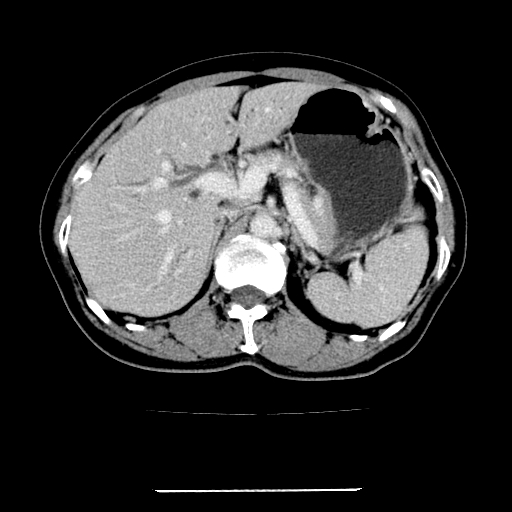

标题: CT22301:女,67岁,上腹部疼痛一周伴皮肤黄染,无发热。 [打印本页]

女,67岁,上腹部疼痛一周伴皮肤黄染,无发热。

左叶肝内胆管结石,并远端肝内胆管扩张。

考虑:肝内胆管结石继发肝内胆管扩张,右肾旋转不良。

肝内外胆管结石并肝内胆管扩张。

建议薄层观察,除外肝门部胆管细胞癌

考虑肝胆管癌;胰头占位?【形态失常,体积增大】

1、肝门高密度影下层面和胰头层面可见轻度胆管扩张,而静脉和延迟期均未见扫描完胰头,不能完全排除胰头占位。2、肝门部高密度影,考虑钙化或结石。

考虑肝门胆管癌伴门脉左支受侵包埋,建议mrcp进一步检查。